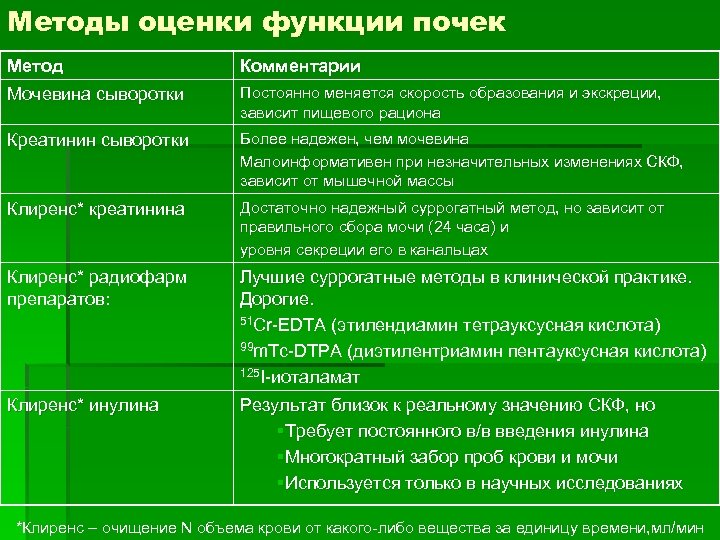

Методы оценки функции почек Метод Комментарии Мочевина сыворотки Постоянно меняется скорость образования и экскреции, зависит пищевого рациона Креатинин сыворотки Более надежен, чем мочевина Малоинформативен при незначительных изменениях СКФ, зависит от мышечной массы Клиренс* креатинина Достаточно надежный суррогатный метод, но зависит от правильного сбора мочи (24 часа) и уровня секреции его в канальцах Клиренс* радиофарм препаратов: Лучшие суррогатные методы в клинической практике. Дорогие. 51 Cr-EDTA (этилендиамин тетрауксусная кислота) 99 m. Tc-DTPA (диэтилентриамин пентауксусная кислота) 125 I-иоталамат Клиренс* инулина Результат близок к реальному значению СКФ, но §Требует постоянного в/в введения инулина §Многократный забор проб крови и мочи §Используется только в научных исследованиях *Клиренс – очищение N объема крови от какого-либо вещества за единицу времени, мл/мин